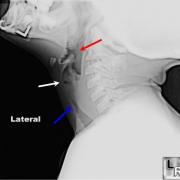

- Viral laryngotracheobronchitis: > 95% of cases, typically infants from 6 months to 2 years, most commonly in winter and early spring, classic “steeple sign” on anterior/posterior neck plain films; if recurrent or persistent consider endoscopy to rule out an underlying anatomic abnormality by visualization of the airway.

Imaging

- Know that imaging studies may play a role in identifying the site of lesion as well as ruling out extrinsic and intrinsic lesions compressing the airway.

- Understand the role that plain radiographs of the neck and/or chest, fluoroscopy with or without barium, and occasionally the use of computed tomography and/or magnetic resonance imaging plays to assess for extrinsic masses impacting the airway.

- Must consider the possibility of an underlying anatomic abnormality of the subglottis. AP and lateral neck/chest films are indicated. Strongly consider endoscopy to visualize and stage the subglottis if films are positive or croup continues.